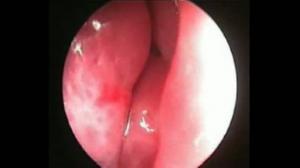

Endoscopie nasale pré-opératoire en cas d'échec d'une chirurgie antérieure

Par : Dr Jean-Marie PIATON (Paris)

Chaîne : Voies lacrymales